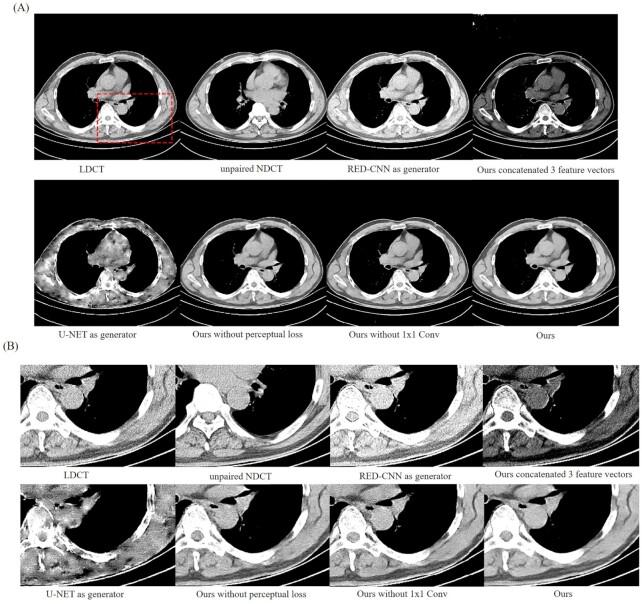

Low-dose computed tomography (LDCT) denoising is an indispensable procedure in the medical imaging field, which not only improves image quality, but can mitigate the potential hazard to patients caused by routine doses. Despite the improvement in performance of the cycle-consistent generative adversarial network (CycleGAN) due to the well-paired CT images shortage, there is still a need to further reduce image noise while retaining detailed features. Inspired by the residual encoder-decoder convolutional neural network (RED-CNN) and U-Net, we propose a novel unsupervised model using CycleGAN for LDCT imaging, which injects a two-sided network into selective kernel networks (SK-NET) to adaptively select features, and uses the patchGAN discriminator to generate CT images with more detail maintenance, aided by added perceptual loss. Based on patch-based training, the experimental results demonstrated that the proposed SKFCycleGAN outperforms competing methods in both a clinical dataset and the Mayo dataset. The main advantages of our method lie in noise suppression and edge preservation.

低剂量计算机断层扫描(LDCT)去噪是医学成像领域不可或缺的一项操作,它不仅能提高图像质量,还能减轻常规剂量对患者造成的潜在危害。尽管由于配对良好的CT图像短缺,循环一致生成对抗网络(CycleGAN)的性能有所提升,但仍需要在保留细节特征的同时进一步降低图像噪声。受残差编码器-解码器卷积神经网络(RED-CNN)和U-Net的启发,我们提出了一种用于LDCT成像的新型无监督模型,该模型使用CycleGAN,将双边网络注入选择性内核网络(SK-NET)以自适应选择特征,并使用PatchGAN鉴别器生成具有更多细节保留的CT图像,同时添加感知损失作为辅助。基于基于补丁的训练,实验结果表明,所提出的SKFCycleGAN在临床数据集和梅奥数据集中均优于竞争方法。我们方法的主要优点在于噪声抑制和边缘保留。